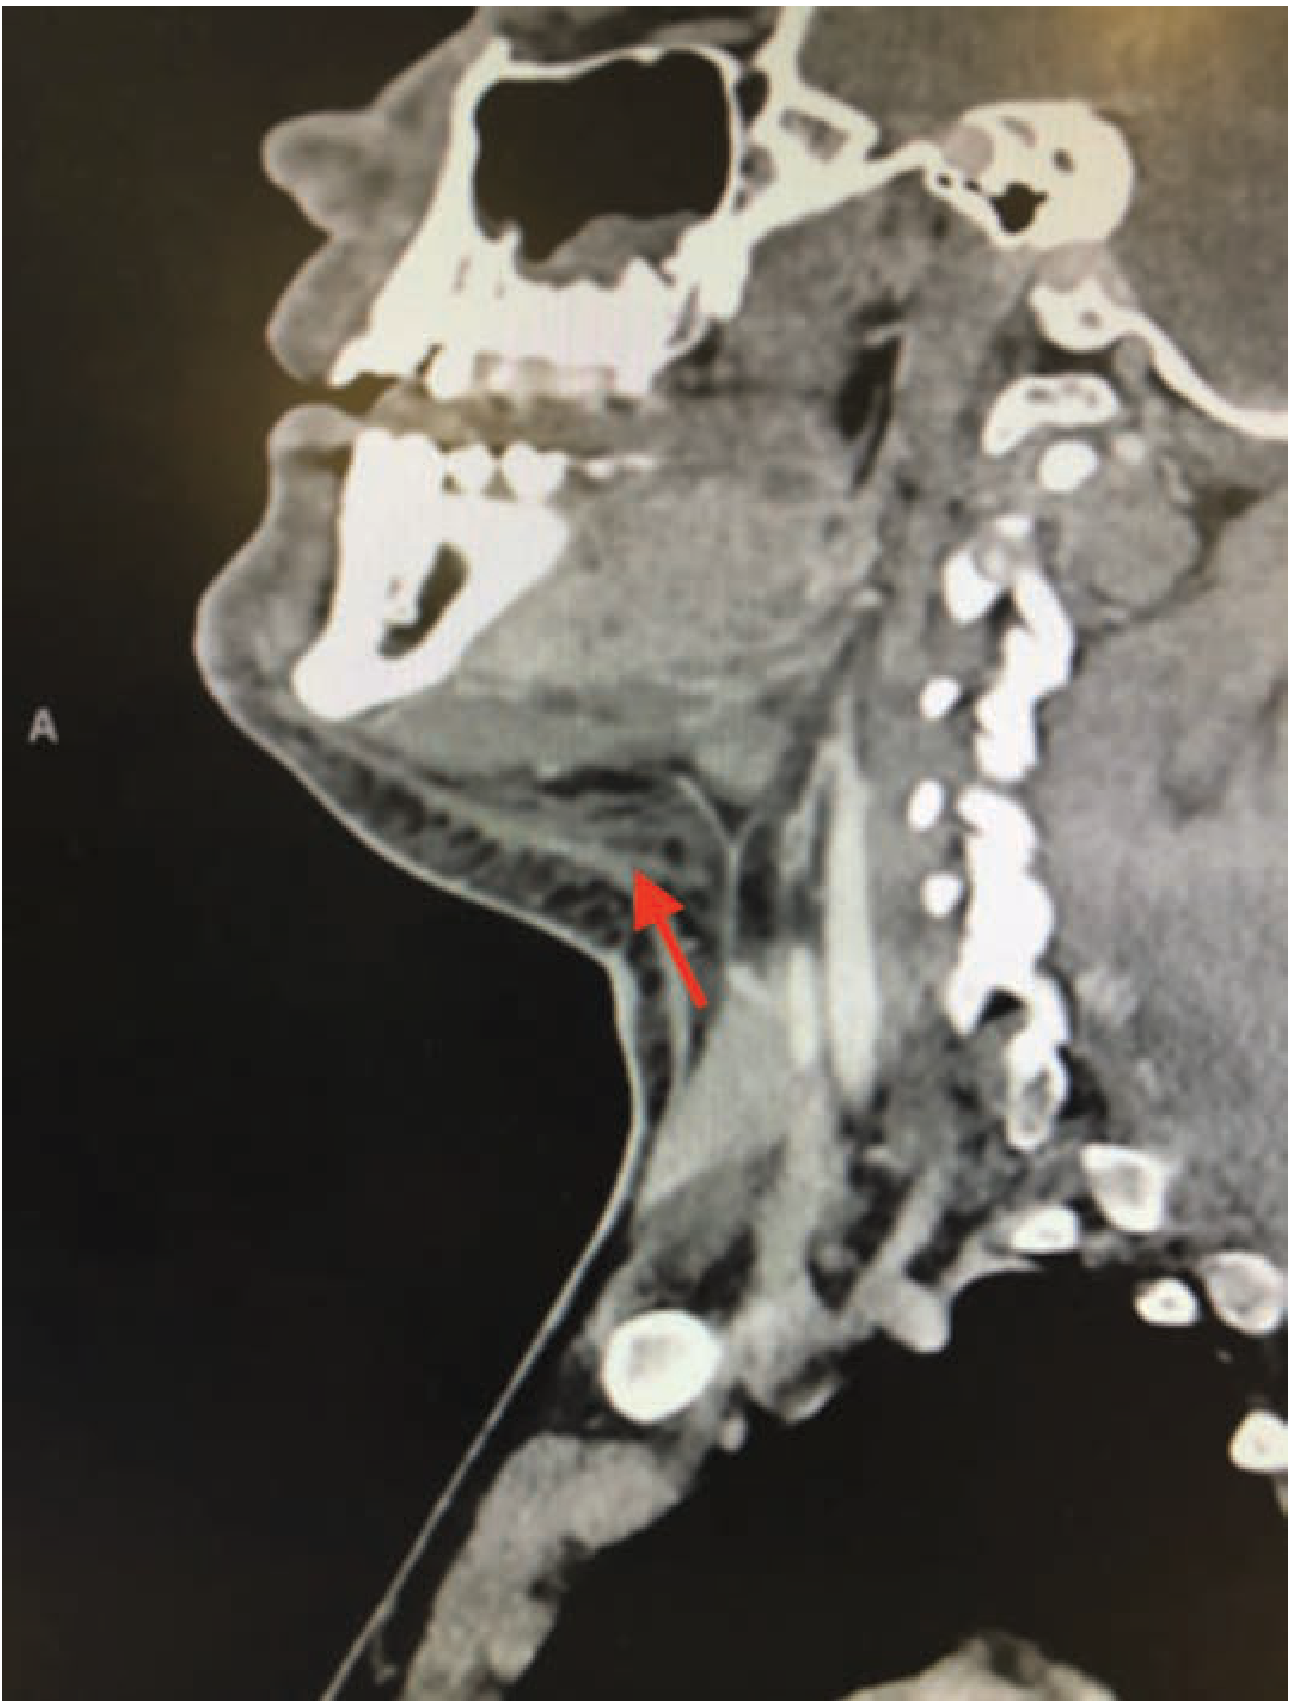

Sagittal CT scan showing soft tissue stranding and inflammation in the submandibular space (red arrow) β€” Ludwig's angina

Sagittal CT scan showing soft tissue stranding and inflammation in the submandibular space (arrow) β€” Tintinalli's Emergency Medicine

• Contrast-enhanced CT is the imaging of choice

• Shows: soft tissue stranding, thickening, gas within fascial planes (gas = anaerobic organisms), extent of spread

• Helps guide surgical drainage planning